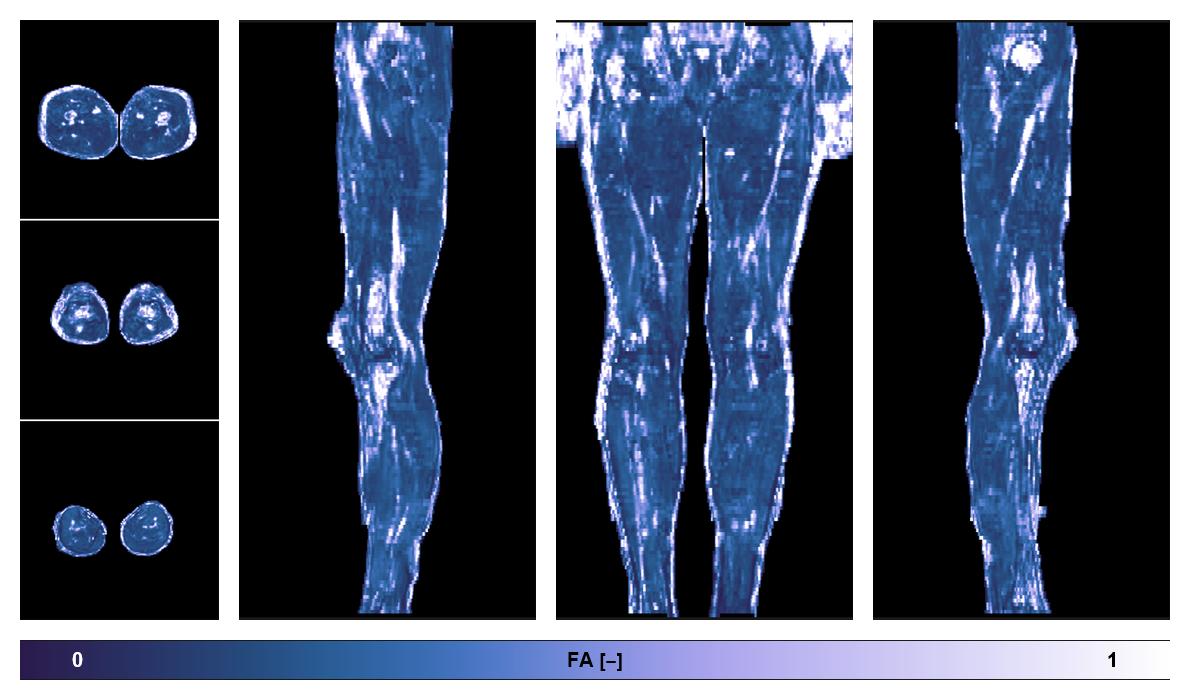

Diffusion tensor imaging

Diffusion weighted imaging with IVIM and DTI fitting to obtain muscle microstructure and muscle architecture, for information look here».

• Fractional anisotropy

IVIM corrected whole leg muscle fractional anisotropy obtained from diffusion tensor imaging.